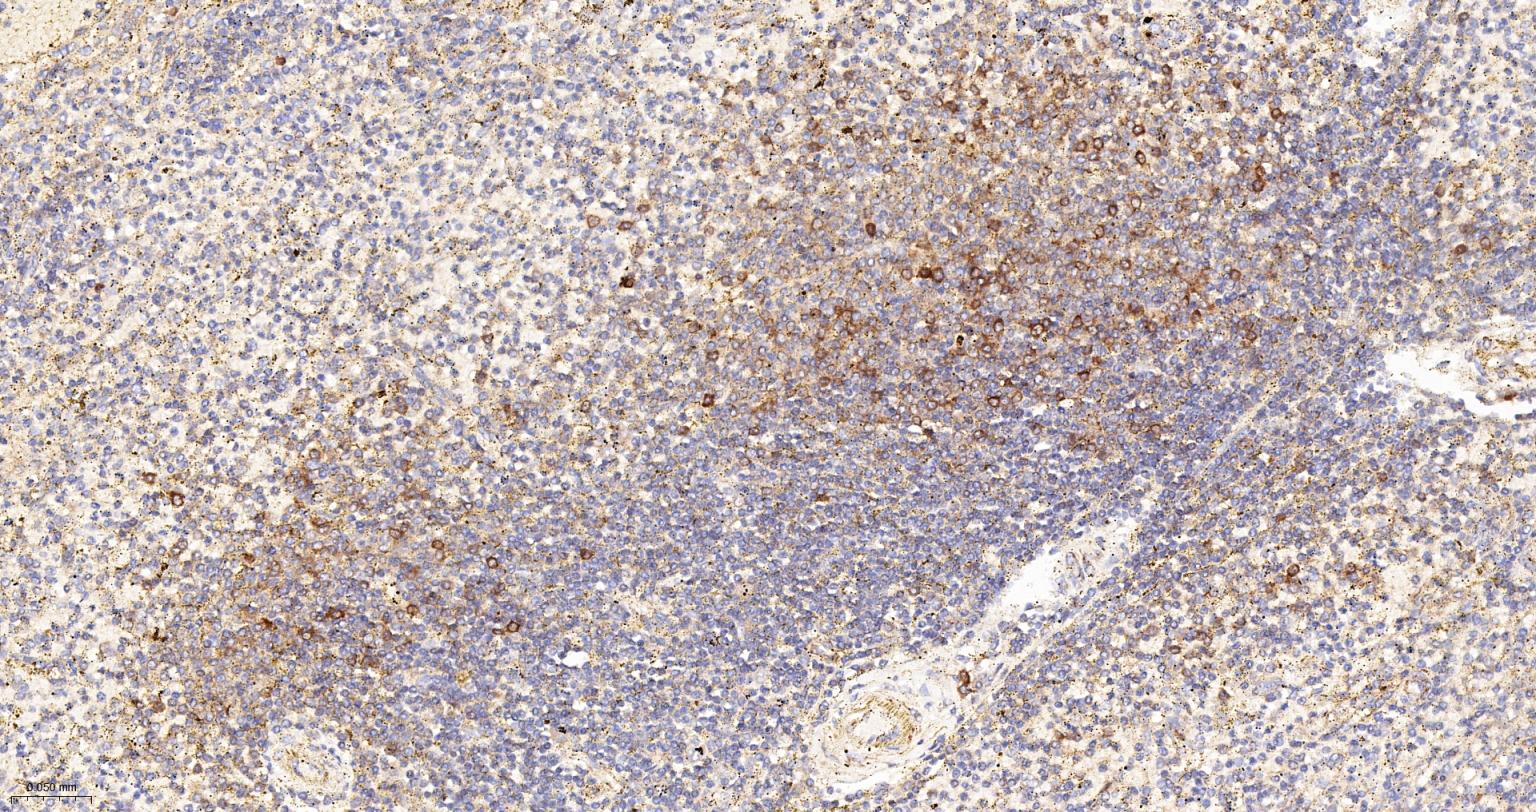

Paraformaldehyde-fixed, paraffin embedded Human Spleen; Antigen retrieval by boiling in sodium citrate buffer (pH6.0) for 15 min; Antibody incubation with Cytochrome C Monoclonal Antibody, Unconjugated(bsm-52050R) at 1:200 overnight at 4°C, followed by conjugation to the SP Kit (Rabbit, SP-0023) and DAB (C-0010) staining.